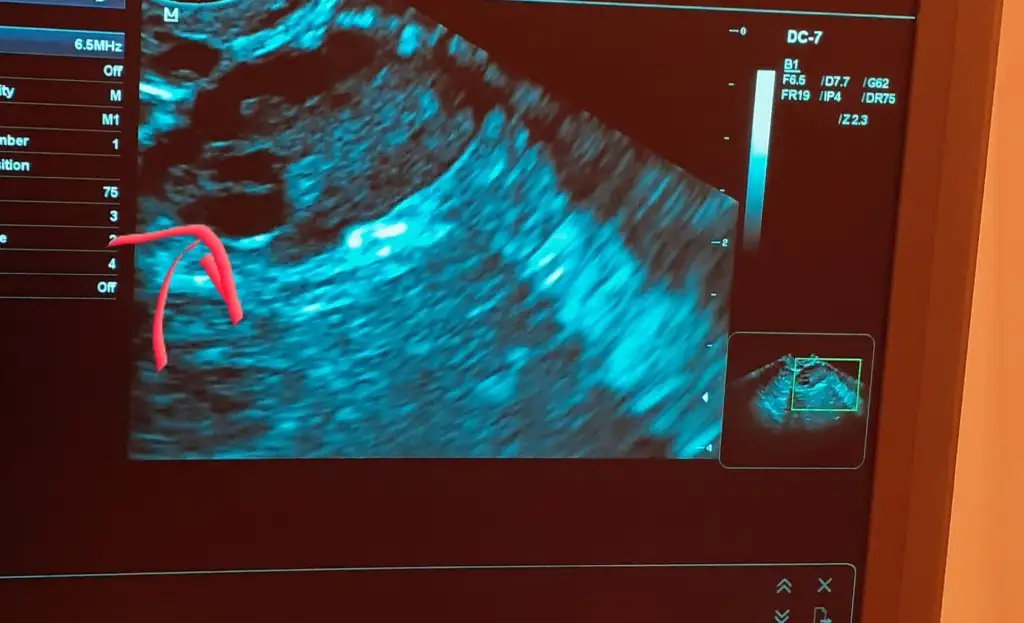

Kizlar arakadasim bakti adetin 15. Gunundeym sizce bu ikisi yumurtami pkoyum

Eklentiler

• 20200419_171708.webp

20200419_171708.webp

31,5 KB · Görüntüleme: 49